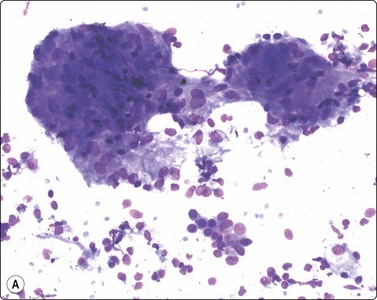

Criteria for diagnosis (Fig. 18.17)

Low cell yield; irregular tissue fragments of haphazardly arranged spindle cells,

Elongated, blunt-ended, mildly irregular hyperchromatic nuclei with inconspicuous nucleoli,

Poorly defined cytoplasm, which in some cases in the Giemsa stain is delineated by metachromatic stroma between the cells,

Single spindle cells with bipolar or long and wispy cytoplasm,

Plasmacytoid lymphocytes, plasma cells, lymphocytes and plentiful tingible-body macrophages.

image image image

Fig. 18.17 (A) Tissue fragment of Kaposi’s sarcoma, showing crowded, spindle shaped cells with hyperchromatic, blunt-ended nuclei (Giemsa, x200); (B) Tissue fragment of spindle cells, with poorly defined cytoplasm Giemsa, x400); (C) Single spindle cells with cigar-shaped bland nuclei, and granular chromatin (Pap, x400) Kaposi’s sarcoma.